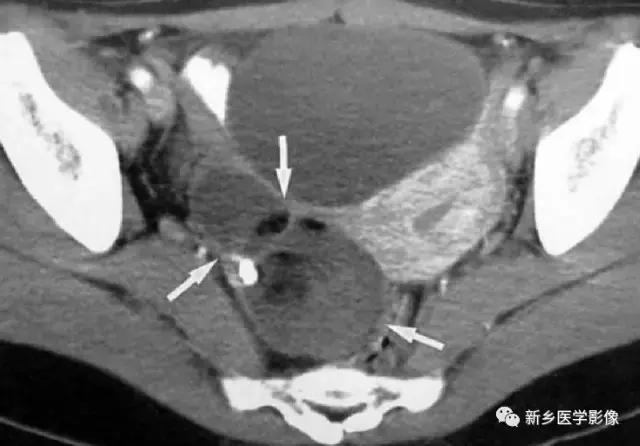

子宫平滑肌瘤(纤维瘤)

主要位于盆腔内,表现为不均一的点状钙化